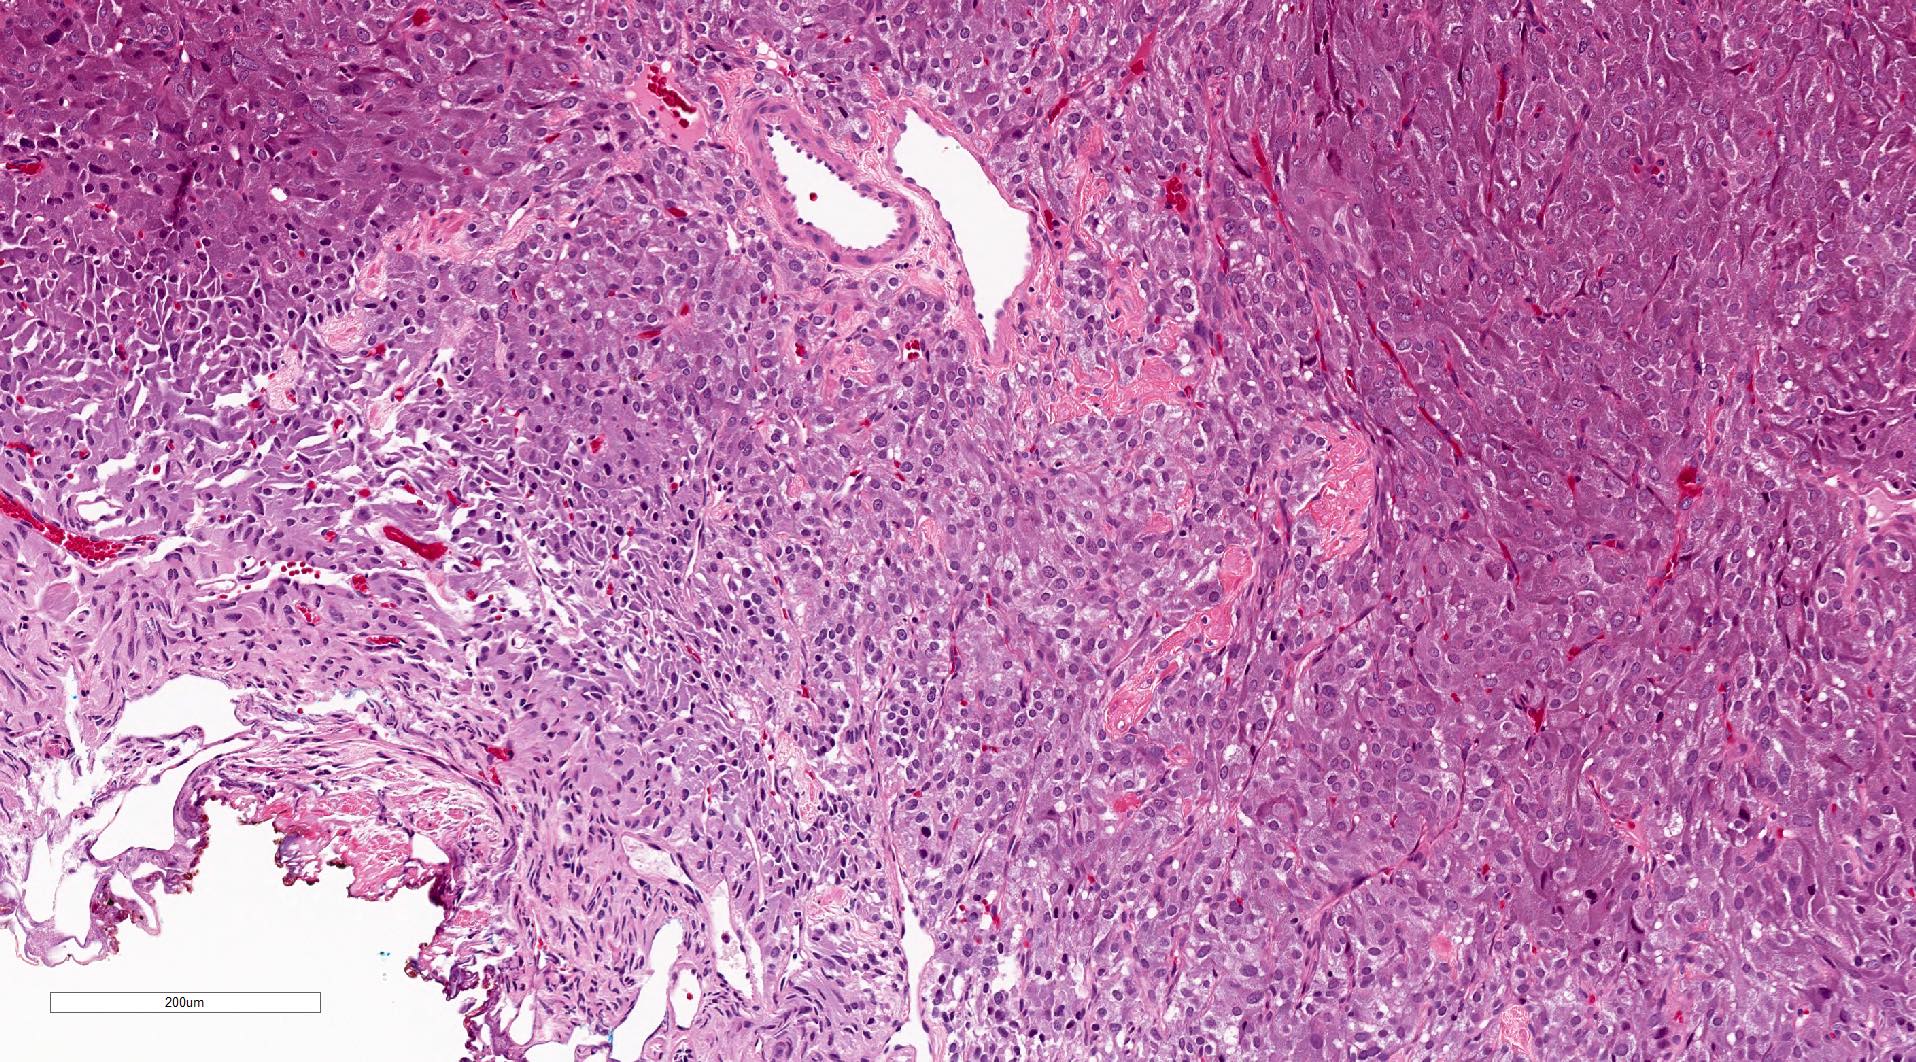

Microscopic (histologic) description

- Typical morphology: epithelioid cells with abundant, eosinophilic / amphophilic, granular cytoplasm and round / ovoid, vesicular / salt and pepper nuclei, arranged in a nested / zellballen pattern and separated by fibrovascular septae with sustentacular cells (Am J Surg Pathol 2004;28:94, World J Clin Cases 2014;2:591, Endocr Pathol 2022;33:90)

- May have focal pleomorphism, nuclear hyperchromasia, low mitotic activity or clear cytoplasm

Microscopic (histologic) images

Contributed by Theodorus H. van der Kwast, M.D., Ph.D., Michelle R. Downes, M.D., Debra L. Zynger, M.D. and David Cohen, M.B.B.Ch., M.D.

- Microscopic description: This specimen shows an unencapsulated, monomorphous population of round tumor cells in a nested / zellballen pattern with delicate vascular septa and intervening extravasated red blood cells. It predominantly involves the lamina propria of the bladder but in 1 tissue piece clearly involves muscularis propria. The tumor cells have abundant amphophilic cytoplasm and vesicular chromatin with occasional small nucleoli. There is no necrosis, diffuse growth pattern or vascular space invasion identified. The mitotic count is (maximally) 1/10 high power fields. Immunohistochemistry shows the tumor cells to be positive for GATA3 with strong and diffuse expression of synaptophysin and chromogranin, as well as retention of SDHB staining. The tumor cells are negative for AE1 / AE3, HMWK and p63. The Ki67 proliferation index is < 1%. S100 shows faint nuclear and cytoplasmic staining with occasional sustentacular cells identified.

- Microscopic description: Sections show unremarkable surface urothelium with a lesion in the deep lamina propria comprised of large eosinophilic cells with hyperchromatic, focally enlarged nuclei with occasional intranuclear inclusions. A fine vascular plexus is identified in some areas. Necrosis and hemorrhage are not identified. Mitotic rate = 1/10 high power fields (field of view [FOV] = 0.55 mm). The lesion extends to the cauterized base of the specimen. Immunostains confirm the lesion expresses synaptophysin, chromogranin and GATA3. SDHB is retained. AE1 / AE3, CD45, p63 and NKX3.1 are negative.